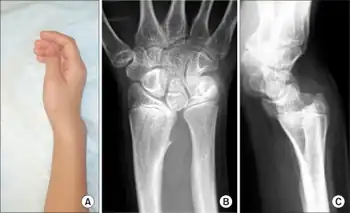

| Madelung deformation, a type of bone malformation associated with both SHOX and SHOXY genes mutations. | |

It is a congenital subluxation or dislocation of the ulna's distal end, due to malformation of the bones. Sometimes, minor abnormalities of other bone structures, often caused by disease or injury, such as a fracture of the distal end of the radius with upward displacement of the distal fragment. The deformity varies in degree from a slight protrusion of the lower end of the ulna, to complete dislocation of the inferior radio-ulnar joint with marked ulnar deviation of the hand. Severe deformities are associated with congenital absence or hypoplasia of the radius.

The male:female rate of this disorder is 1:4. The incidence is unknown, and there is no described racial predominance. Even though Madelung's Deformity is considered a congenital disorder, symptoms sometimes aren't seen until adulthood. In most cases, symptoms find their onset during midchildhood. At this age, the relatively slower growth of the ulnar and palmar part of the radius, leads to an increasingly progressive deformity. Pain and deformity are the main symptoms patients present with.[1] Typical clinical presentation consists of a short forearm, anterior-ulnar bow of the radius and a forward subluxation of the hand on the forearm. As mentioned before, the severity of the disorder varies greatly, which also leads to a spectrum of presentation.

Madelung deformity of the wrist is caused by a growth disturbance in the inferior volar part of the epiphysial growth plate in the distal radius, resulting in a volar placed slope of the lunate facet and scaphoid facet. This produces volar translation of the hand and wrist. The ulna continues growing straight, resulting in a dorsally prominent distal ulna. It occurs predominantly in adolescent females, who present with pain, decreased range of motion, and deformity. It often has a genetic cause and is associated with mesomelic dwarfism and a mutation on the X chromosome. Attempts can be made to treat the deformity surgically by addressing the deforming bone and fibrous bands called "Vickers ligament". This is an abnormal ligament formed between the Lunate bone of the wrist and the radius and is found in 91% of cases of Madelung's deformity.

Diagnosis is normally confirmed by X-rays.